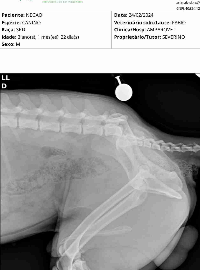

Ele deslocou um ossinho da coluna e não esta conseguindo andar.

Foi levado em uma ong fez raio x e tomou medicamento porem a ong passou um orçamento de R$1000 (há confirmar) para operar ele fora os medicamentos que irá precisar depois da cirurgia.